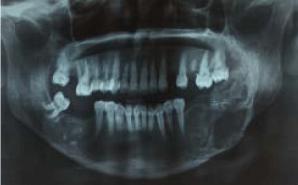

Primary Hyperparathyroidism Revealed by a Brown Tumor: A Series of 9 Cases

Gorgi K* 1 Chaouche M 1

Brown tumors are bone manifestations of hyperparathyroidism (HPT). They usually occur in severe forms accompanied by signs of periosteal bone resorption. Their treatment mainly relies on parathyroidectomy.

We report a series of 9 cases of primary hyperparathyroidism revealed by a brown tumor. These clinical cases highlight the importance of phosphocalcic assessment in the presence of any bone swelling suggestive of a brown tumor.

Keywords: Brown Tumor;